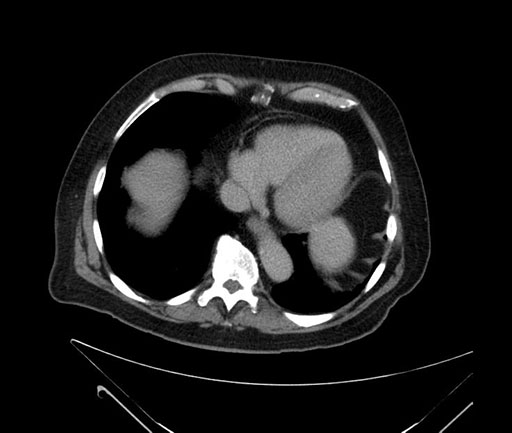

Axial - stented